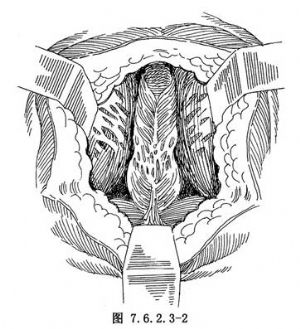

1.切口及顯露尿道球海綿體肌 若球部尿道狹窄靠近陰囊根部,可採用會陰正中直切口;若靠近膜部尿道,則宜採用“U”形切口。按層切開皮膚及皮下組織至球海綿體肌表面。在其表面鈍性遊離周圍組織,使球海綿體肌完全顯露於切口之內(圖7.6.2.3-2)。